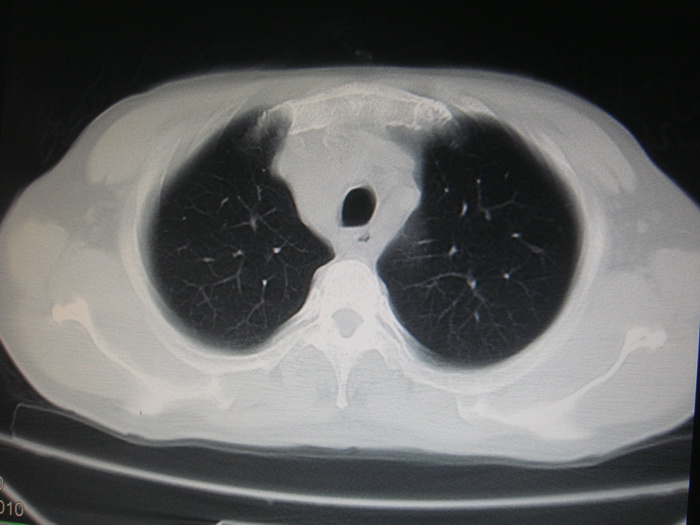

标题: CT28366:男性,45岁,偶尔发现右颈部肿块行胸部CT扫描。 [打印本页]

男性,45岁,偶尔发现右颈部肿块行胸部ct扫描。

两肺多发结节灶及纵膈淋巴结肿大考虑为转移

两肺多发性转移瘤,纵隔淋巴结转移。

两肺多发性转移瘤,纵隔淋巴结转移。食道中上段管壁似乎增厚,作相关检查。

两肺多发性转移瘤,前上纵隔淋巴结转移。